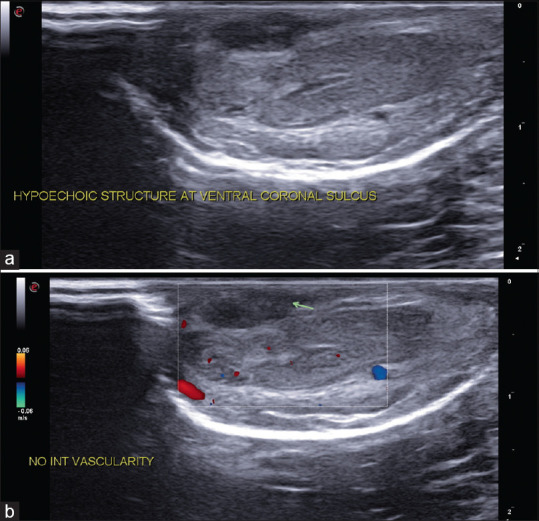

Penile Mondor's disease co-occurring with sclerosing lymphangitis: A double whammy.